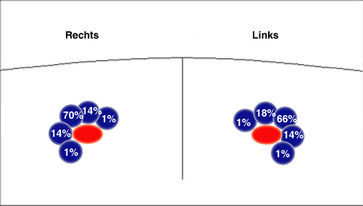

Die in der Anästhesie verbreitete Punktion der distalen Vena jugularis ist komplikationsträchtig und sollte vermieden werden. Normalerweise liegt die Vena jugularis lateral der A. carotis.

Bei der schädelnahen Punktion muß der Kopf nach links gedreht werden, weil sonst das Kinn im Weg ist. Dadurch rotiert die Vene vor die Arterie und das Lumen wird schlitzförmig.